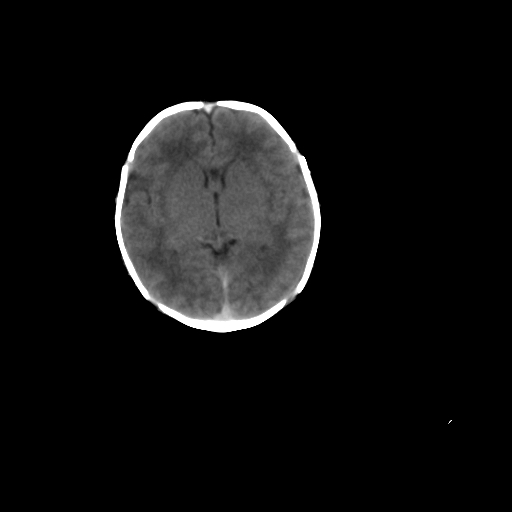

男,12天,自然分娩,其母发现右顶部头皮包块逐渐增大。

疑问:患儿脑白质密度比较低,基底节区密度比较高,类似于“双圈征”脑沟密度也偏高。该婴儿可有别的异常吗?反射正常吗?评分能达到5分吗?如果正常,就随诊观察吧。不正常要考虑到缺血缺氧性脑病。

鉴别:骨膜下血肿,一般为产伤,应用产钳之类的吧